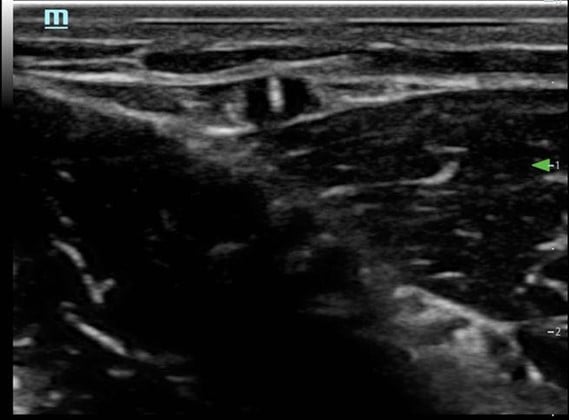

- Visualize the vein in cross-section (Fig. 3)

Figure 3. Short axis approach: vein visualized in cross axis